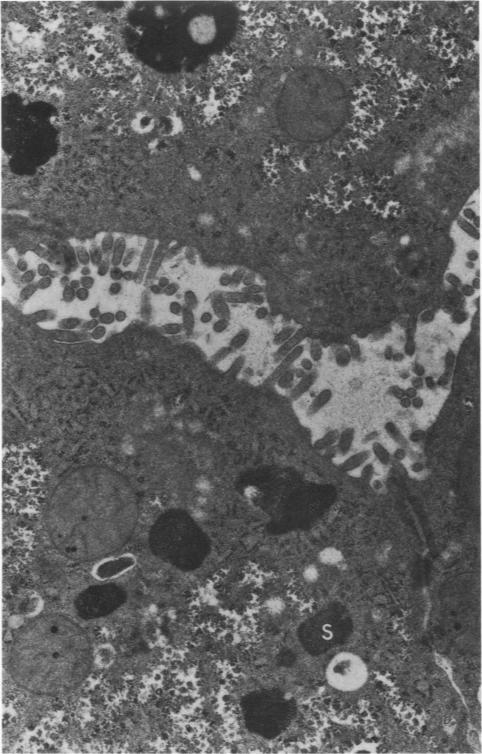

Ultrastructural aspects of iron storage, transport and metabolism.

Observations on subcutaneous macrophages. Phago-cytosis of iron-dextran and ferritin synthesis.

COMMENTARY ON HEMOSIDERIN.

SIDEROBLASTIC ANAEMIA, MITOCHONDRIA AND ERYTHROBLASTIC IRON.